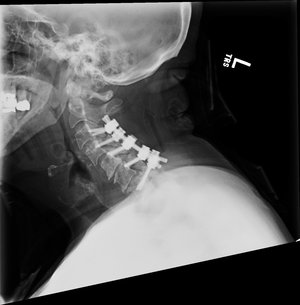

4-level ACDF

C3-7